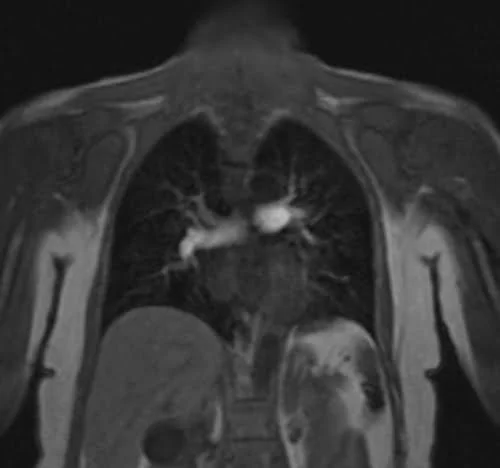

The care bolus image looks similar to the T1 localizer scans, with contrast in the blood vessels appearing bright during image acquisition.

CARE BOLUS SEQUENCE USED IN CHEST ANGIOGRAPHY